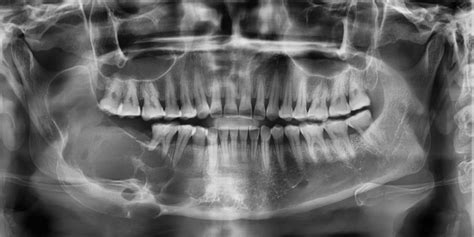

El principal método para detectar un quiste maxilar es a través de una radiografía, en la que se puede observar una mancha de color oscuro en el hueso. Una vez que el dentista sepa de la presencia del quiste, es posible que solicite pruebas adicionales, tales como una tomografía computarizada o una biopsia, que le permitan tener una información más completa y detallada sobre el tipo de quiste, la extensión del mismo y sus características.